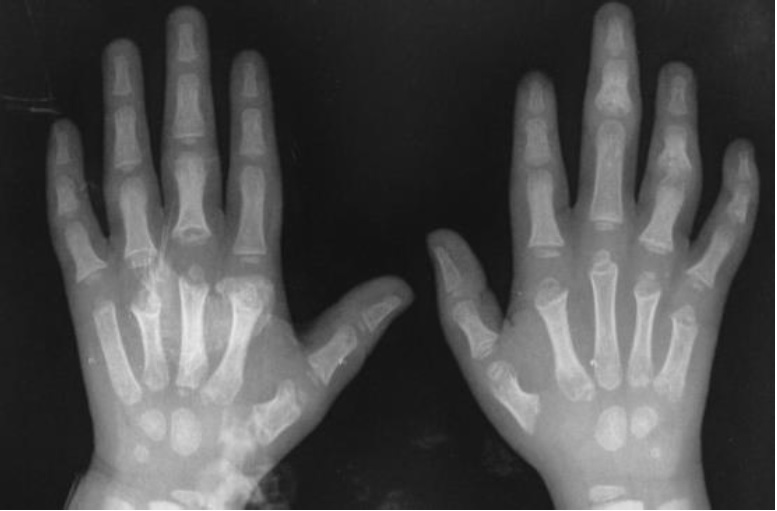

Em ultrassonografia de membros inferiores, foram confirmados abscessos nos pés. Na investigação, foi diagnosticada a osteomielite que acometia úmero, tíbia, ossos dos pés e das mãos bilateralmente. Foi feita drenagem contínua de lojas de secreção purulenta na região das tíbias.

As radiografias confirmaram o diagnóstico de osteomielite (Figuras 1 a 5). Em culturas de secreção tibial, foram isolados Escherichia coliESBL e Proteus mirabilis, sensíveis a imipenem e amicacina. Dessa forma, optou-se por tratamento com antibioticoterapia parenteral, ao longo de tempo prolongado de internação.

Foram realizadas radiografias seriadas e o consequente tratamento cirúrgico de drenagem de abscessos e colocação de drenos. Não foram realizadas cintilografias e ressonância magnética, uma vez que o diagnóstico se fez tardiamente com o quadro já instalado de forma importante. Esses últimos exames contribuiriam para um diagnóstico mais precoce. Não foi realizada biópsia óssea das áreas acometidas, exame eventualmente necessário1. Em alguns casos, radiografias podem estar normais4, porém, em outros, como no caso descrito, elas se apresentam alteradas, conforme visto nas imagens.

Em seguimento ambulatorial, o paciente apresenta padrão radiológico melhor, como evidenciado em radiografia recente, ausente o atraso no crescimento, uma vez que placas epifisárias não se mostram afetadas. Permaneceu em antibioticoterapia estendida por mais cinco meses além do programado na alta hospitalar e isento de complicações novas por osteomielite. Internações devido às crises álgicas ou outros tipos de infecções já foram registradas.